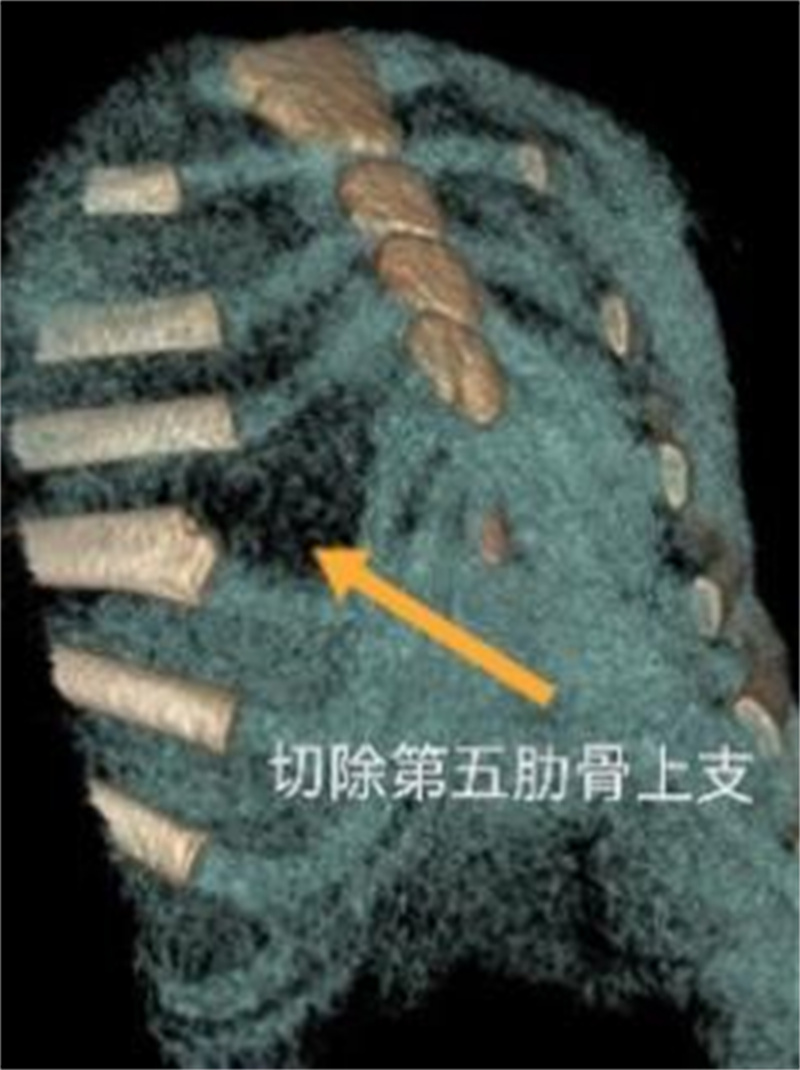

可以,目前采用悬吊腔镜叉状肋切除术。叉状肋大部分分叉的上部肋软骨发育较细,且生长方向与其他正常肋骨走行角度不一致,这是导致胸壁凸起的原因之一。手术时,通常需切除分叉的上部软骨及分叉的部分硬骨。